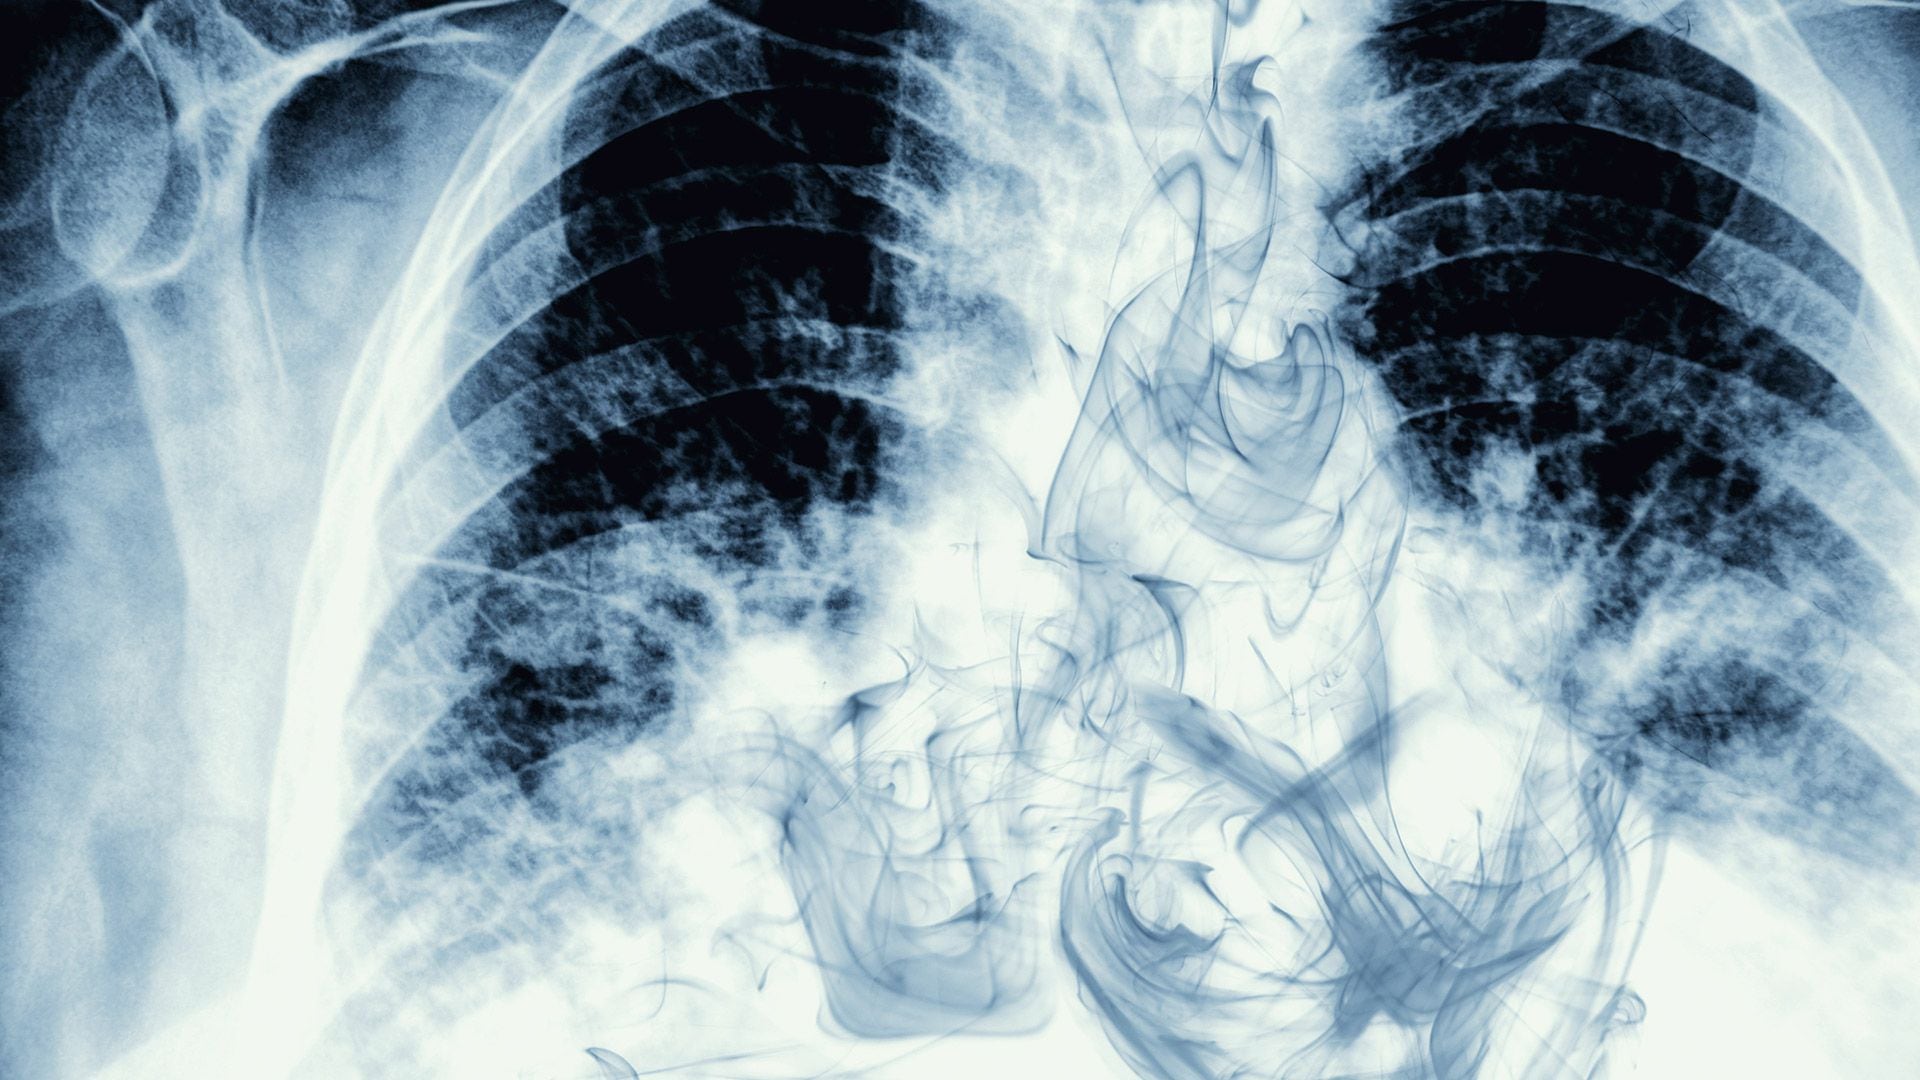

Si conseguís pasar 72 horas sin fumar, vas a notar que te es más fácil respirar. Esto se debe a que los bronquios -los sacos de aire de los pulmones que pueden irritarse y dañarse con el humo- empiezan a relajarse. También es posible que sientas un poco de energía al aumentar los niveles de oxígeno en la sangre.

Al cabo de tres meses, la función pulmonar aumenta hasta un 10%, según el NHS. Para entonces, la tos, las sibilancias y los problemas respiratorios empiezan a remitir. Pemberton reveló que su tos, causada por décadas de tabaquismo, desapareció “al cabo de unas dos semanas”.

Sin embargo, también advirtió que es probable desarrollar tos después de dejar de fumar y explicó que es sólo una señal de que los pulmones están empezando a funcionar de nuevo. “Algunas personas tienen tos después de dejar de fumar, pero esto se debe a que los cilios, los pelos de los pulmones, están trabajando y tratando de deshacerse de la suciedad. En realidad, es una señal de que los pulmones están funcionando”, detalló.

Tras una década sin fumar, el riesgo de muerte por cáncer de pulmón se va a haber reducido a la mitad, en comparación con un fumador. Según la organización benéfica Cancer Research, cuando se fuma, los cigarrillos liberan más de 5.000 sustancias químicas diferentes.

El tabaquismo también influye en otros tipos de cáncer: los expertos creen que fumar provoca al menos 15 tipos de cáncer. Puede ser la causa del cáncer de boca y garganta, recto, hígado y páncreas, por nombrar algunos.